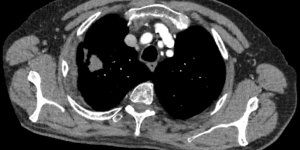

Mass in Medial Clavicle | Cases

Published on Jan 15, 2021

Lump over Medial clavicular region close to SCJ 57 female Reports slow growing lump in chest region for over 5 years. No trauma. Gets some shoulder pain. Has been having osteopathy for shoulder. Full shoulder ROM on examination. Non tender lump. Mild SCJ tenderness. Clinician requested MRI scans. Retrospective and current investigations below. [...] Read more